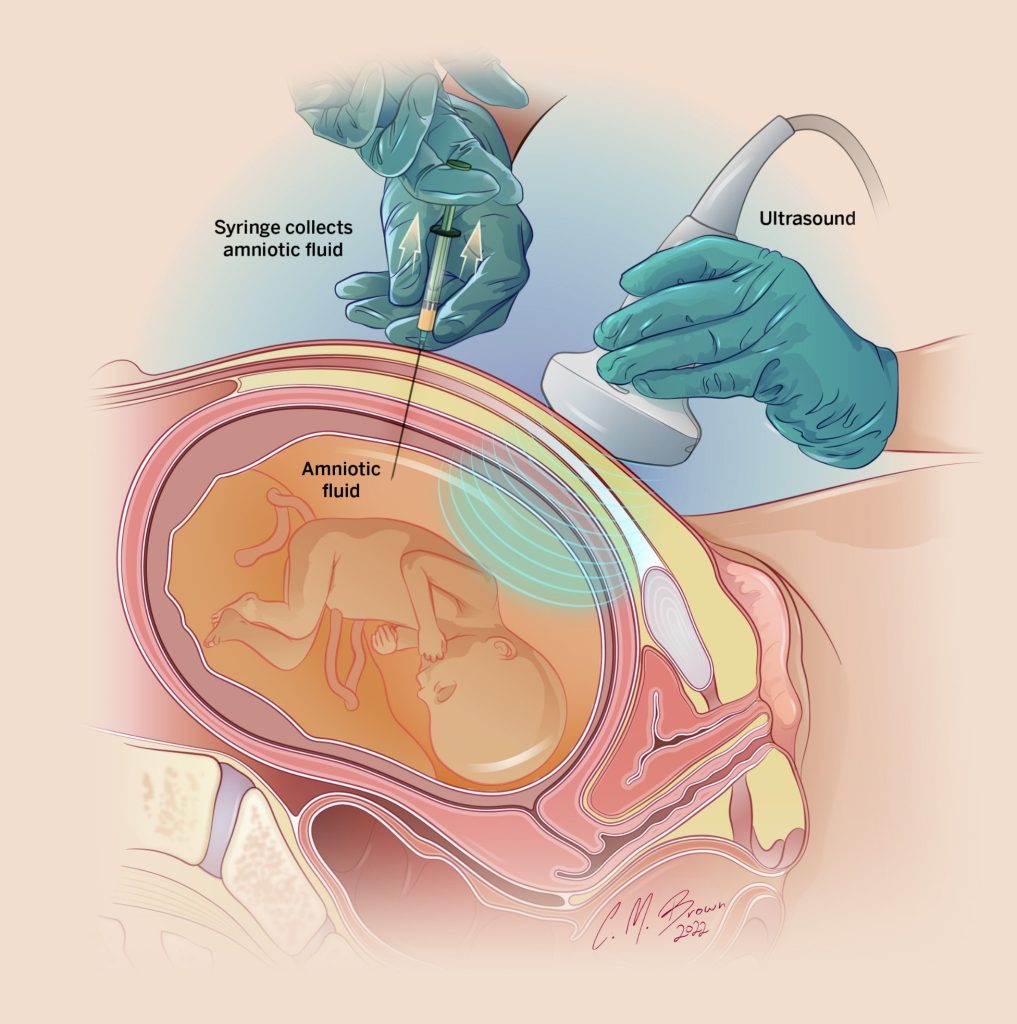

Khi nào cần chọc ối?

Nguyên tắc trong y học bào thai là phân tầng nguy cơ.

Chọc ối được cân nhắc khi:

- Có bất thường tim cấu trúc

- Có nhiều dấu hiệu mềm

- Kết quả sàng lọc nguy cơ cao

Nếu chỉ có động mạch dưới đòn phải lạc chỗ siêu âm thai đơn độc và NIPT nguy cơ thấp, chọc ối không phải chỉ định thường quy.

Nếu chọc ối thì xét nghiệm gì?

Khi có chỉ định chọc ối, các xét nghiệm cần làm gồm:

Karyotype nhiễm sắc thể để phát hiện lệch bội lớn như Down.

Microarray nhiễm sắc thể để phát hiện vi mất đoạn nhỏ như 22q11.2.

Whole Exome Sequencing chỉ cân nhắc khi thai có dị tật cấu trúc phức tạp hoặc nghi ngờ bệnh lý đơn gen. ARSA đơn độc không phải chỉ định làm WES.